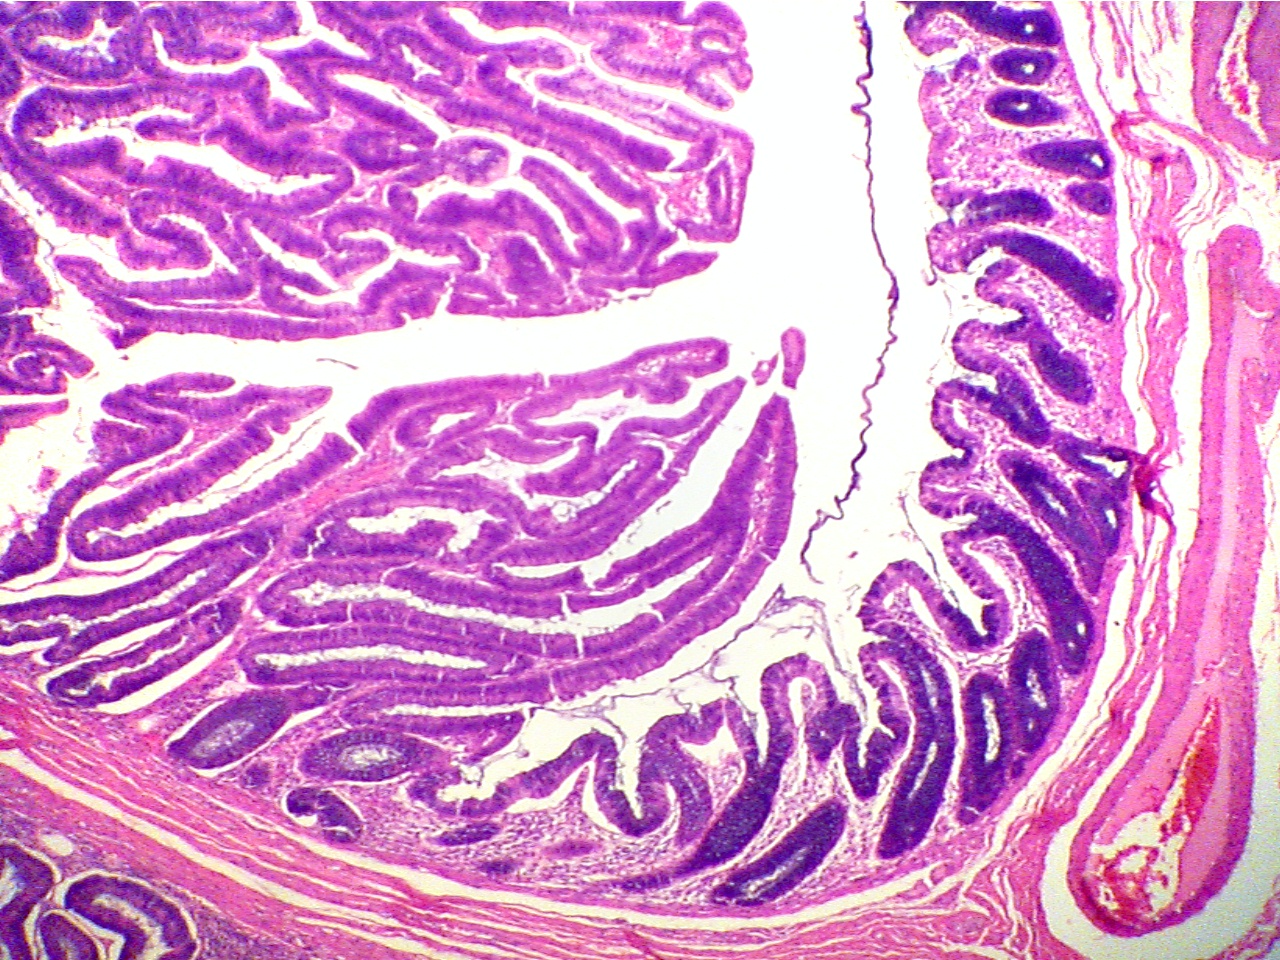

- Adenomatous Polyp of the Colon - Benign (PH 1435) (pp. 114, 116)

Note that the mucosal cells have undergone massive proliferation. However, they remain in their normal though expanded arrangement, remain attached to one another and therefore form a benign tumor. (Compare with Fig. 8-10, p. 93). Compare the thickness of the adenoma mucosa with that of the short piece of normal mucosa.

Adenomatous polyp (40X1.6)

Normal mucosa (thin dark layer) at right, neoplasia (very thick

dark purple layers) at left